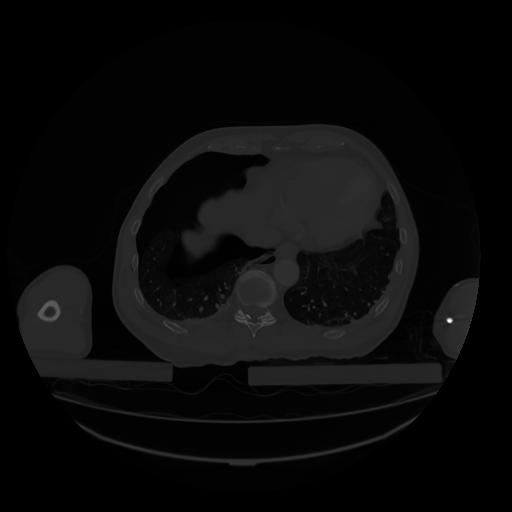

28 CUERPO,CE,Vol,2.0,CUERPO,,